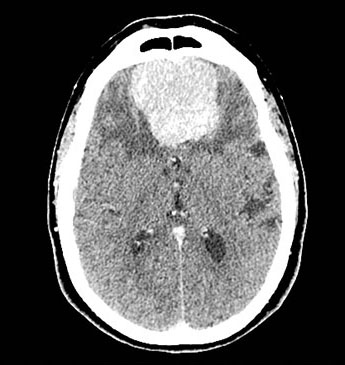

脑膜瘤绝大多数都是良性的,生长缓慢,切除之后不容易复发。但是有一些脑膜瘤却是恶性的,它们可以侵蚀颅骨,把头骨都“吃掉”,还有一些不容易切干净,存在复发的可能。

世界卫生组织(WHO)根据脑膜瘤的良恶性程度,将脑膜瘤分为了三级,I/II/III三级,级别越高,恶性程度越高,越容易侵犯周边的组织,也越容易复发。

这是一个III级的脑膜瘤,这是利用计算机模拟形成的图像,我们可以看到肿瘤已经破坏了患者的头骨。